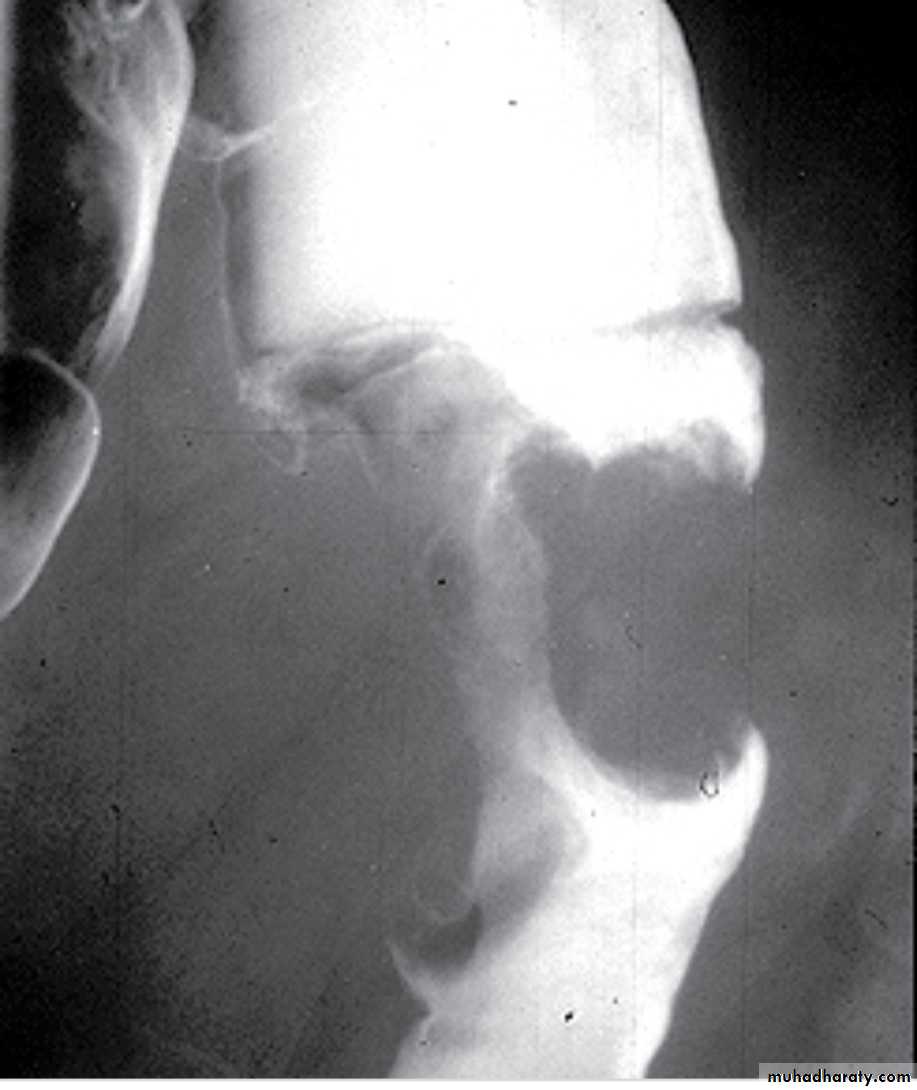

• 3- AP and Lateral views are taken with inverted position(invertogram) .

• Signs of low atresia :

• 1- Multiple air fluid level due to obstruction .

• 2- In AP view the distance between the terminal rectal segment and the marker should not exceed 2 cm.

• 3- In lateral view the terminal air shadow is seen above the pubo-coccygeal line.

• Signs of high atresia

• 1- In AP view the distance more than 2 cm .• 2-In lateral view the terminal air is below the pubo-coccygeal line .

Low type

High type